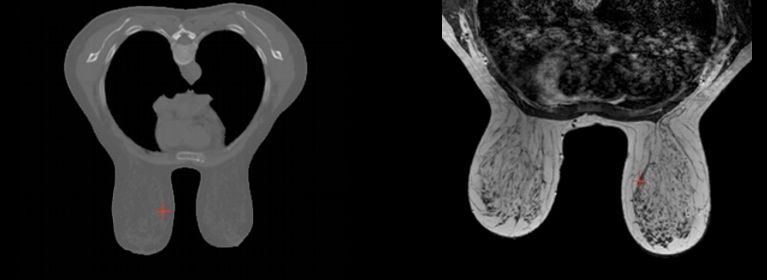

Dentro de esta línea de investigación se ha desarrollado un sistema de seguimiento de lesiones tumorales hepáticas mediante aproximaciones biomecánicas para diagnosis temprana y planificación de tratamiento, basado en la simulación de la deformación que sufre el hígado con la respiración. En esta línea también se está desarrollando un sistema de registro multimodal de imagen (basado en el modelado biomecánico de tejidos de la mama adaptado a paciente) de exploraciones mamográficas mediante MRI (tomografías de resonancia magnética), PET (tomografía por emisión de positrones) y Rayos-X para el diagnóstico precoz y la monitorización del cáncer de mama.